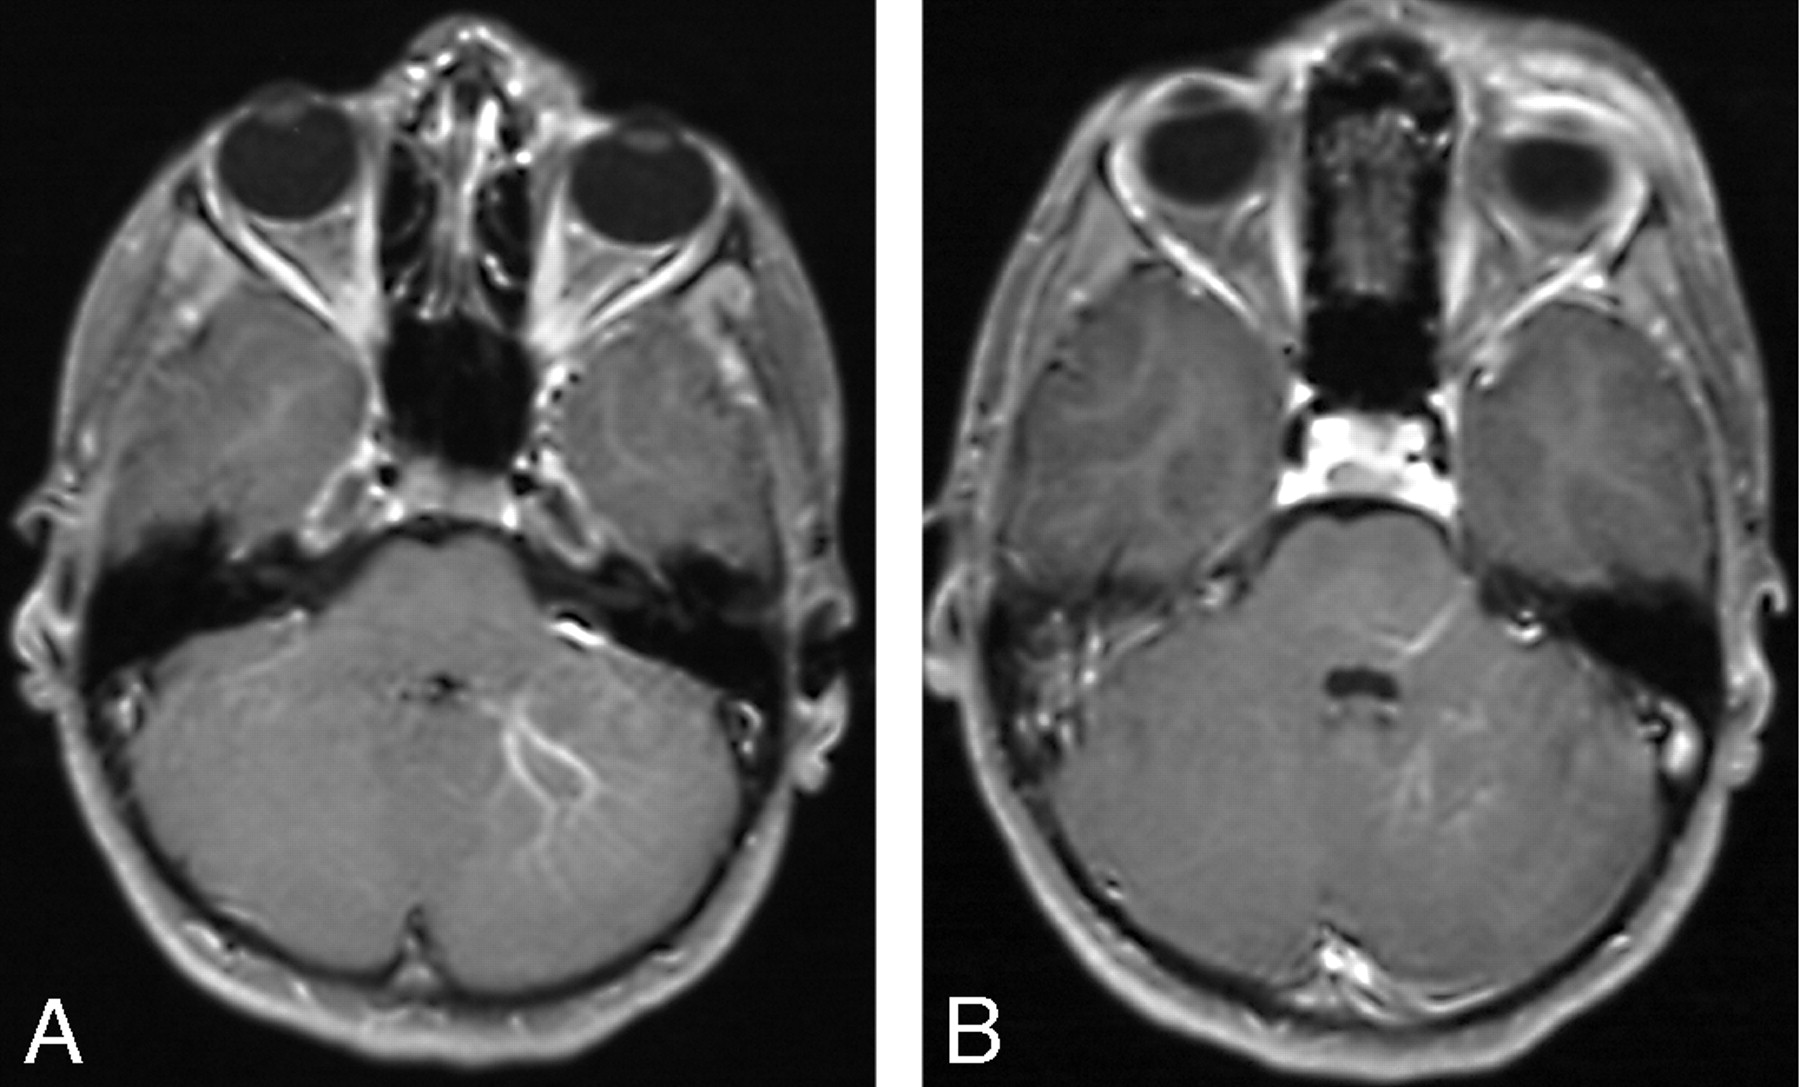

A and B, Postgadolinium axial T1-weighted MR images of a patient with a left preseptal orbitofrontal lymphatic malformation shows ipsilateral posterior fossa DVAs.

A and B, Posterior fossa DVA in another patient is confirmed angiographically. Frontal (A) and lateral (B) venous phase of left vertebral angiogram shows the left cerebellar and left occipital DVAs draining into the left transverse sinus.